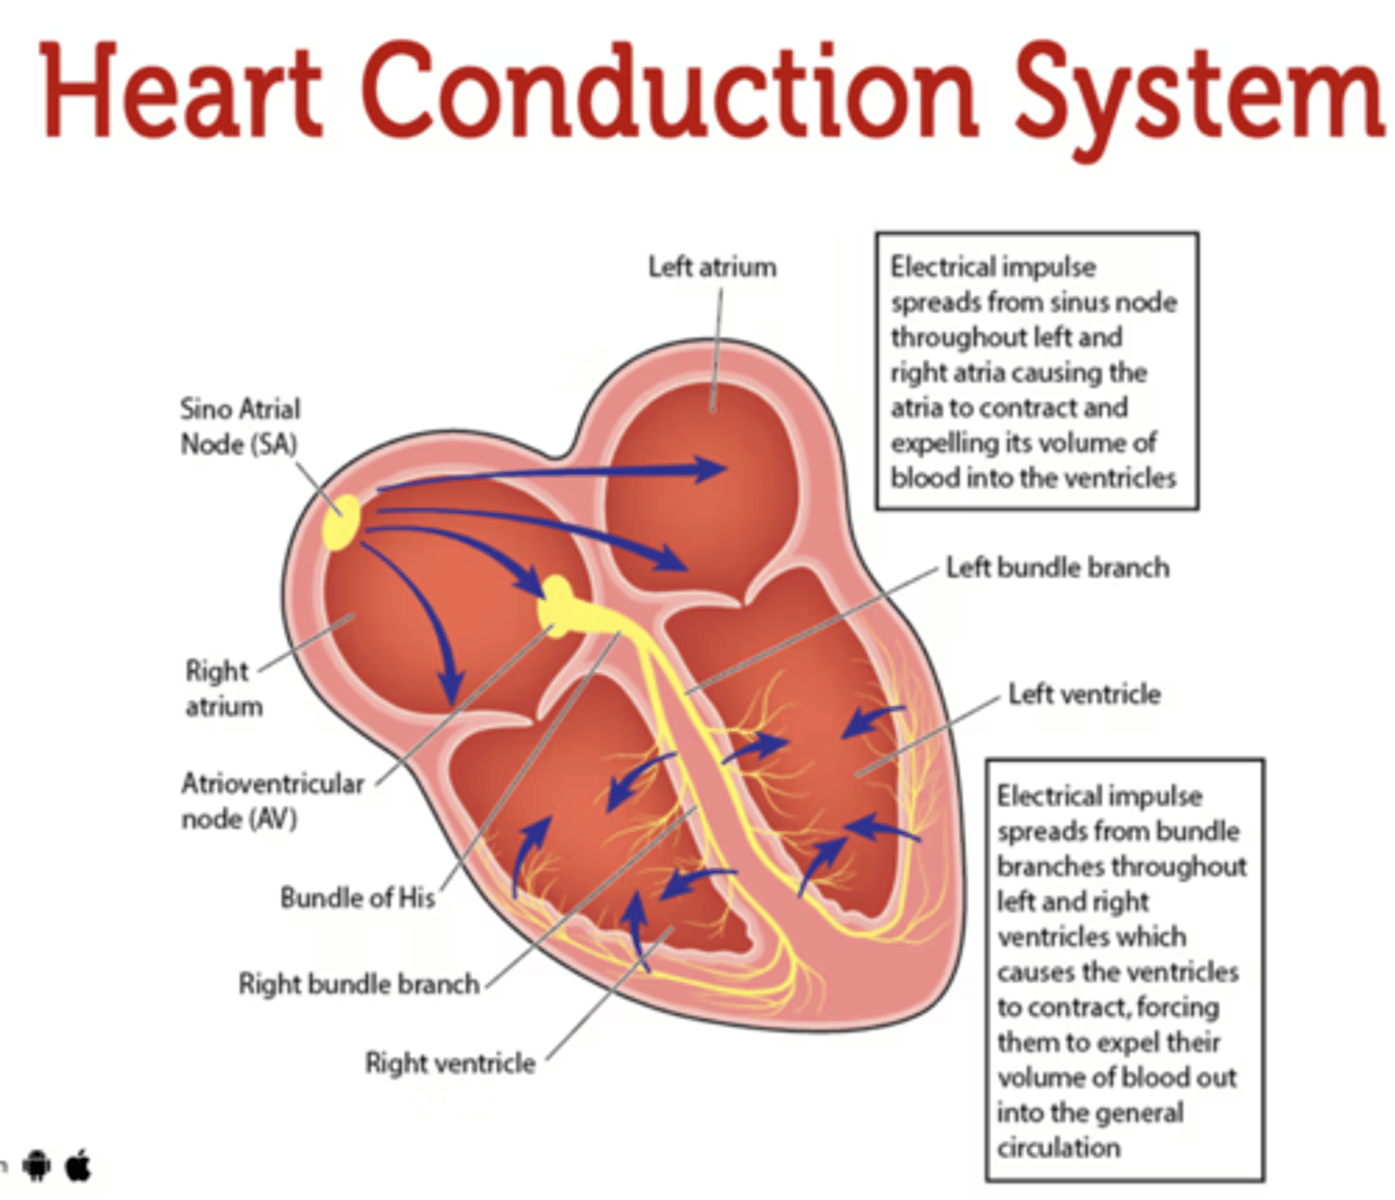

What allows the heart to contract by itself?

The heart possesses a specialized conduction system that gives it the autonomous capacity to contract, allowing it to pump by itself in a correct buffer.

What are the two conduction nodes of the heart conduction system?

. SA node (sinoatrial node)

. AV node (atrioventicular node)

What is the function of the sinoatrial (SA) node?

Pacemaker of the heart

Where is initiated the contraction of the SA node?

SVC (Superior Vena Cava)

passing through the atrium to the AV node

Where is the SA located?

upper wall of the right atrium,

at the junction where the superior vena cava enters

Where is the atrioventricular (AV) node located, and what follows it?

At the level of the atrioventricular septum,

AV node is followed by?

Bundle of Hiss that divides into two branches

Where does Bundle of Hiss ends?

Purkninje fibers

Describe the propagation of waves in the conduction system ?

. SA node sends the initial wave

Passes through the walls of the atria

. Ends at the AV node in the AV septum

. Travels along the Bundle of His

. Reaches Purkinje fibers in the walls of the ventricles

What role does the moderator band play in the conduction system?

Allows the wave to reach the papillary muscles, inducing their contraction simultaneously with that of the ventricles.

REMEMBER: PAPILLARY MUSCLES ACT THROUGH THE CHORDAE TENDINAE TO CONTROL THE TRICUSPID AND MITRAL VALVES.

What is the significance of the Bundle of His in heart conduction?

Branching to the right and left to ensure coordinated contraction of the ventricles.

What are the Purkinje fibers, and what is their function?

specialized conductive fibers in the walls of the ventricles that

facilitate rapid transmission of electrical impulses,

ensuring efficient and synchronized ventricular contraction.

How does the AV node contribute to heart rhythm?

Delays the electrical impulse from the SA node,

ensuring that the atria contract fully to transfer blood to the

ventricles before the ventricles contract.